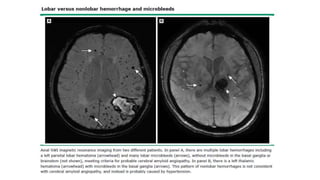

• Enf pequeños vasos cerebrales

arterioescleróticos:

• Regiones subcorticales (ganglios

basales y corona radiada) 

presume menos vasos colaterales

subcorticales en comparación con

rica colateralización de corteza.

• Múltiples infartos lacunares o

lesiones extensas y confluentes de

sust blanca.

• Sinónimos: Enf Binswanger y

demencia vascular isquémica

subcortical.

• Puede haber microinfartos corticales,

neurodegeneración 2ria con

apoptosis  adelgazamiento

cortical.

• Angiopatía amiloide cerebral

(AAC):

• 2do tipo más común de enf de vasos

pequeños cerebrales. Depósitos βA

en AA pequeñas y arteriolas en

leptomeninges y corteza.

• Pérdida integridad vascular 

hemorragias cerebrales grandes ASx,

Sx y pequeñas.

• Hemorragias restringidas a

ubicaciones típicas en corteza o sust

blanca subcortical (lobulares) con

preservación de ganglios basales y el

tronco encefálico.